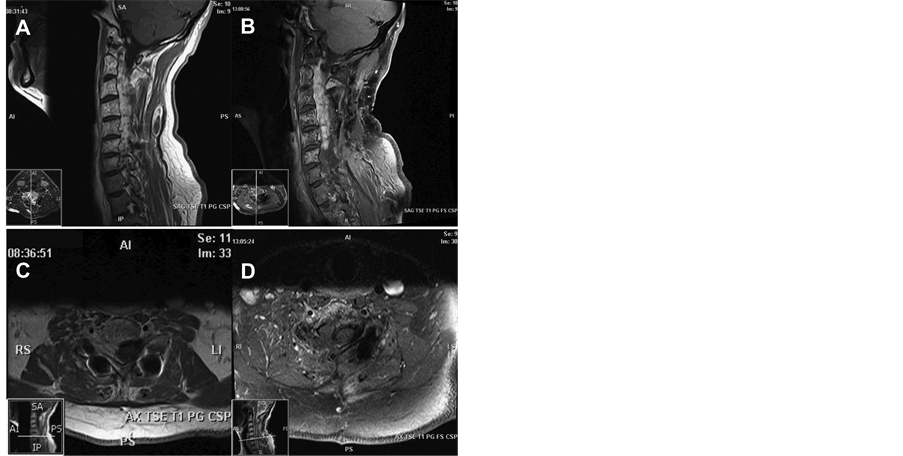

This 51-year-old male presented with history of right arm weakness, had been previously submitted to C3-6 decompressive laminectomy and instrumented posterior fusion at an outside hospital for cervical stenosis. During surgery, a significant vascular malformation was noted and partially resected for spinal cord decompression. The patient presented to our facility with progressive pain and weakness in the C6-8 dermatomes and myotomes. On gross exam, the patient has a confluent dermal port-wine stain vascular anomaly involving the C6 dermatomal distribution and right arm hypertrophy consistent with Klippel-Trenaunay-Weber syndrome (Figure 1). Imaging revealed a vascular malformation involving the majority of the cervical spinal axis with complete involvement of the C2-6 vertebral bodies and all right foraminae down to T1 (Figure 2). The plan was to proceed with endovascular embolization of the symptomatic portion of the vascular malformation and possible surgery or radiosurgery to follow if neurologic recovery is not sufficient. The patient understood that there was no possible curative procedure.

Figure 2. MRI with Sagittal ((A) and (B)) and C7 Axial ((C) and (D)) T1 with contrast images obtained pre- ((A) and (C)) and postoperatively ((B) and (D)) that display the extensive vascular malformation involving the entire cervical spine and the decompressive foraminotomies that were performed for partial resection of the malformation.